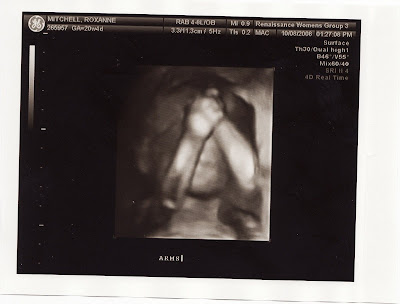

Surprisingly, we also got to see a 3D image of the baby's face.....

Well, we would have had Baby not had arms in front of face, as seen above. After a few jiggles with the ultrasound probe, the technician got him/her to move the arms out of the way.....

Introducing Baby Borrok - I hope it's not creepy to anyone. I think it's adorable, but of course I'm supposed to, right :) Still has an arm up there blocking the side of the face, but this was as good as it got.

Here's a new profile shot - much like the other one, but now we're bigger. 12 ounces. You can see the hand above the forehead. We also got to see opening and closing of the mouth. They checked for opening and closing the hand, checked all brain anatomy, spinal cord, heart anatomy and function (baby got its first echocardiogram!), liver, bladder, kidneys. It was really amazing how detailed they could get on all this.